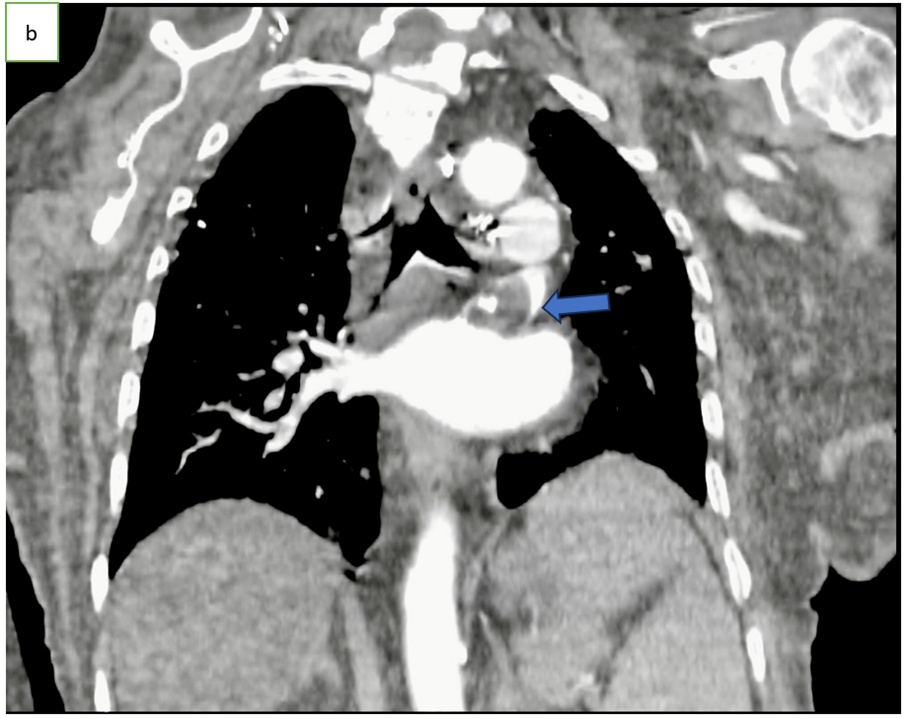

Figure 1: Axial CT scan angiography (a), coronal (b) and sagittal (c) reconstruction, showing an endoluminal thrombi in the pulmonary vein (arrow).

Chest CT angiography is the preferred imaging method, typically showing a well-defined, hypodense endoluminal thrombus in a pulmonary vein [1,3], outlined by contrast but not enhancing after injection [1].